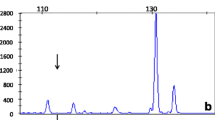

The MLPA results obtained for the three patient samples in which no exon could be amplified confirmed the presence of a large deletion encompassing all exons of the GALT gene, as no signal was produced for any of the GALT exons (Fig. 2). The parents of these patients were confirmed as deletion carriers. Samples from the three patients apparently homozygous for p.Lys285Asn and three of their parents in whom no mutation was detected by exon sequencing were also analyzed by MLPA and found to be heterozygous carriers of the same deletion. MLPA analysis further indicated lack of amplification of the probe targeted to the 5’ non-translated region of the adjacent IL11RA gene located 3.5 kb downstream of the GALT stop codon (Fig. 2). We repeated the MLPA analysis using the newer version of the MLPA kit (P156-B1), which contains a probe for exon 17 of the upstream gene DNAI1, and found that this probe was amplified in individuals carrying the deletion at comparable levels to normal individuals, indicating that the upstream border of the deletion lies within the 132.5 kb region between GALT and exon 17 of DNAI1 (Supplementary Fig. S1).

Traces generated using the SALSA MLPA kit P156 GALT, for a patient homozygous for the new deletion, one of the parents and a normal control. Arrows indicate absent or reduced signal (red arrows for GALT, green arrows for IL11RA). Exon numbers are shown at the top of the peaks (E1–E11). Reference probes are marked by an asterisk (*)